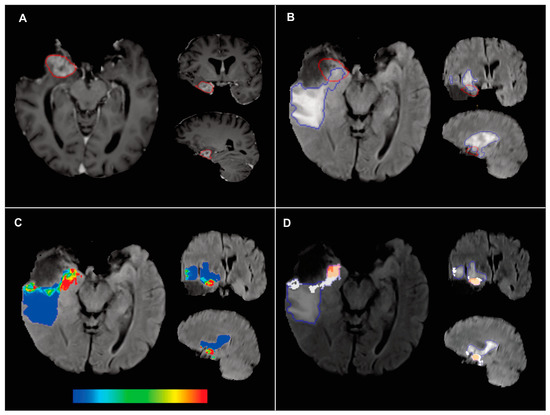

2.6. Probability Maps and Predicted Recurrence Labels